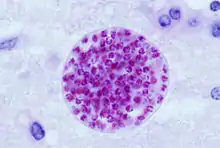

Formation of tissue cysts

Following the initial period of infection characterized by tachyzoite proliferation throughout the body, pressure from the host's immune system causes T. gondii tachyzoites to convert into bradyzoites, the semidormant, slowly dividing cellular stage of the parasite.[36] Inside host cells, clusters of these bradyzoites are known as tissue cysts. The cyst wall is formed by the parasitophorous vacuole membrane.[28]: 343 Although bradyzoite-containing tissue cysts can form in virtually any organ, tissue cysts predominantly form and persist in the brain, the eyes, and striated muscle (including the heart).[28]: 343 However, specific tissue tropisms can vary between intermediate host species; in pigs, the majority of tissue cysts are found in muscle tissue, whereas in mice, the majority of cysts are found in the brain.[28]: 41

Cysts usually range in size between five and 50 µm in diameter,[37] (with 50 µm being about two-thirds the width of the average human hair).[38]

Bradyzoites

Bradyzoites are the slowly dividing stage of the parasite that make up tissue cysts. When an uninfected host consumes a tissue cyst, bradyzoites released from the cyst infect intestinal epithelial cells before converting to the proliferative tachyzoite stage.[28]: 359 Following the initial period of proliferation throughout the host body, tachyzoites then convert back to bradyzoites, which reproduce inside host cells to form tissue cysts in the new host.